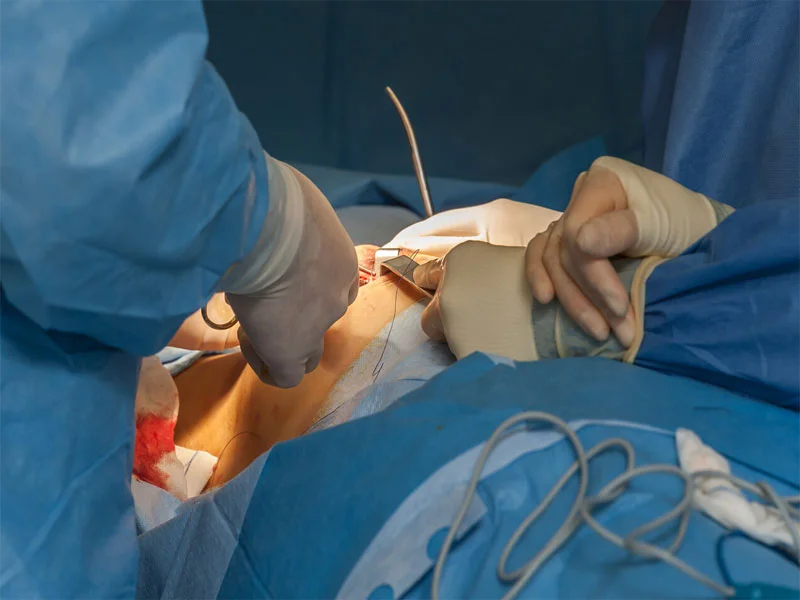

جراحی بازسازی پستان بازآفرینی شکل، حجم و تقارن پستان پس از برداشتن آن است. هدف اصلی این جراحی بازگرداندن ظاهر

پروتز سینه یکی از پرطرفدارترین عملهای زیبایی در سراسر دنیاست. عملی که نه تنها ظاهر فیزیکی را تغییر میدهد، بلکه